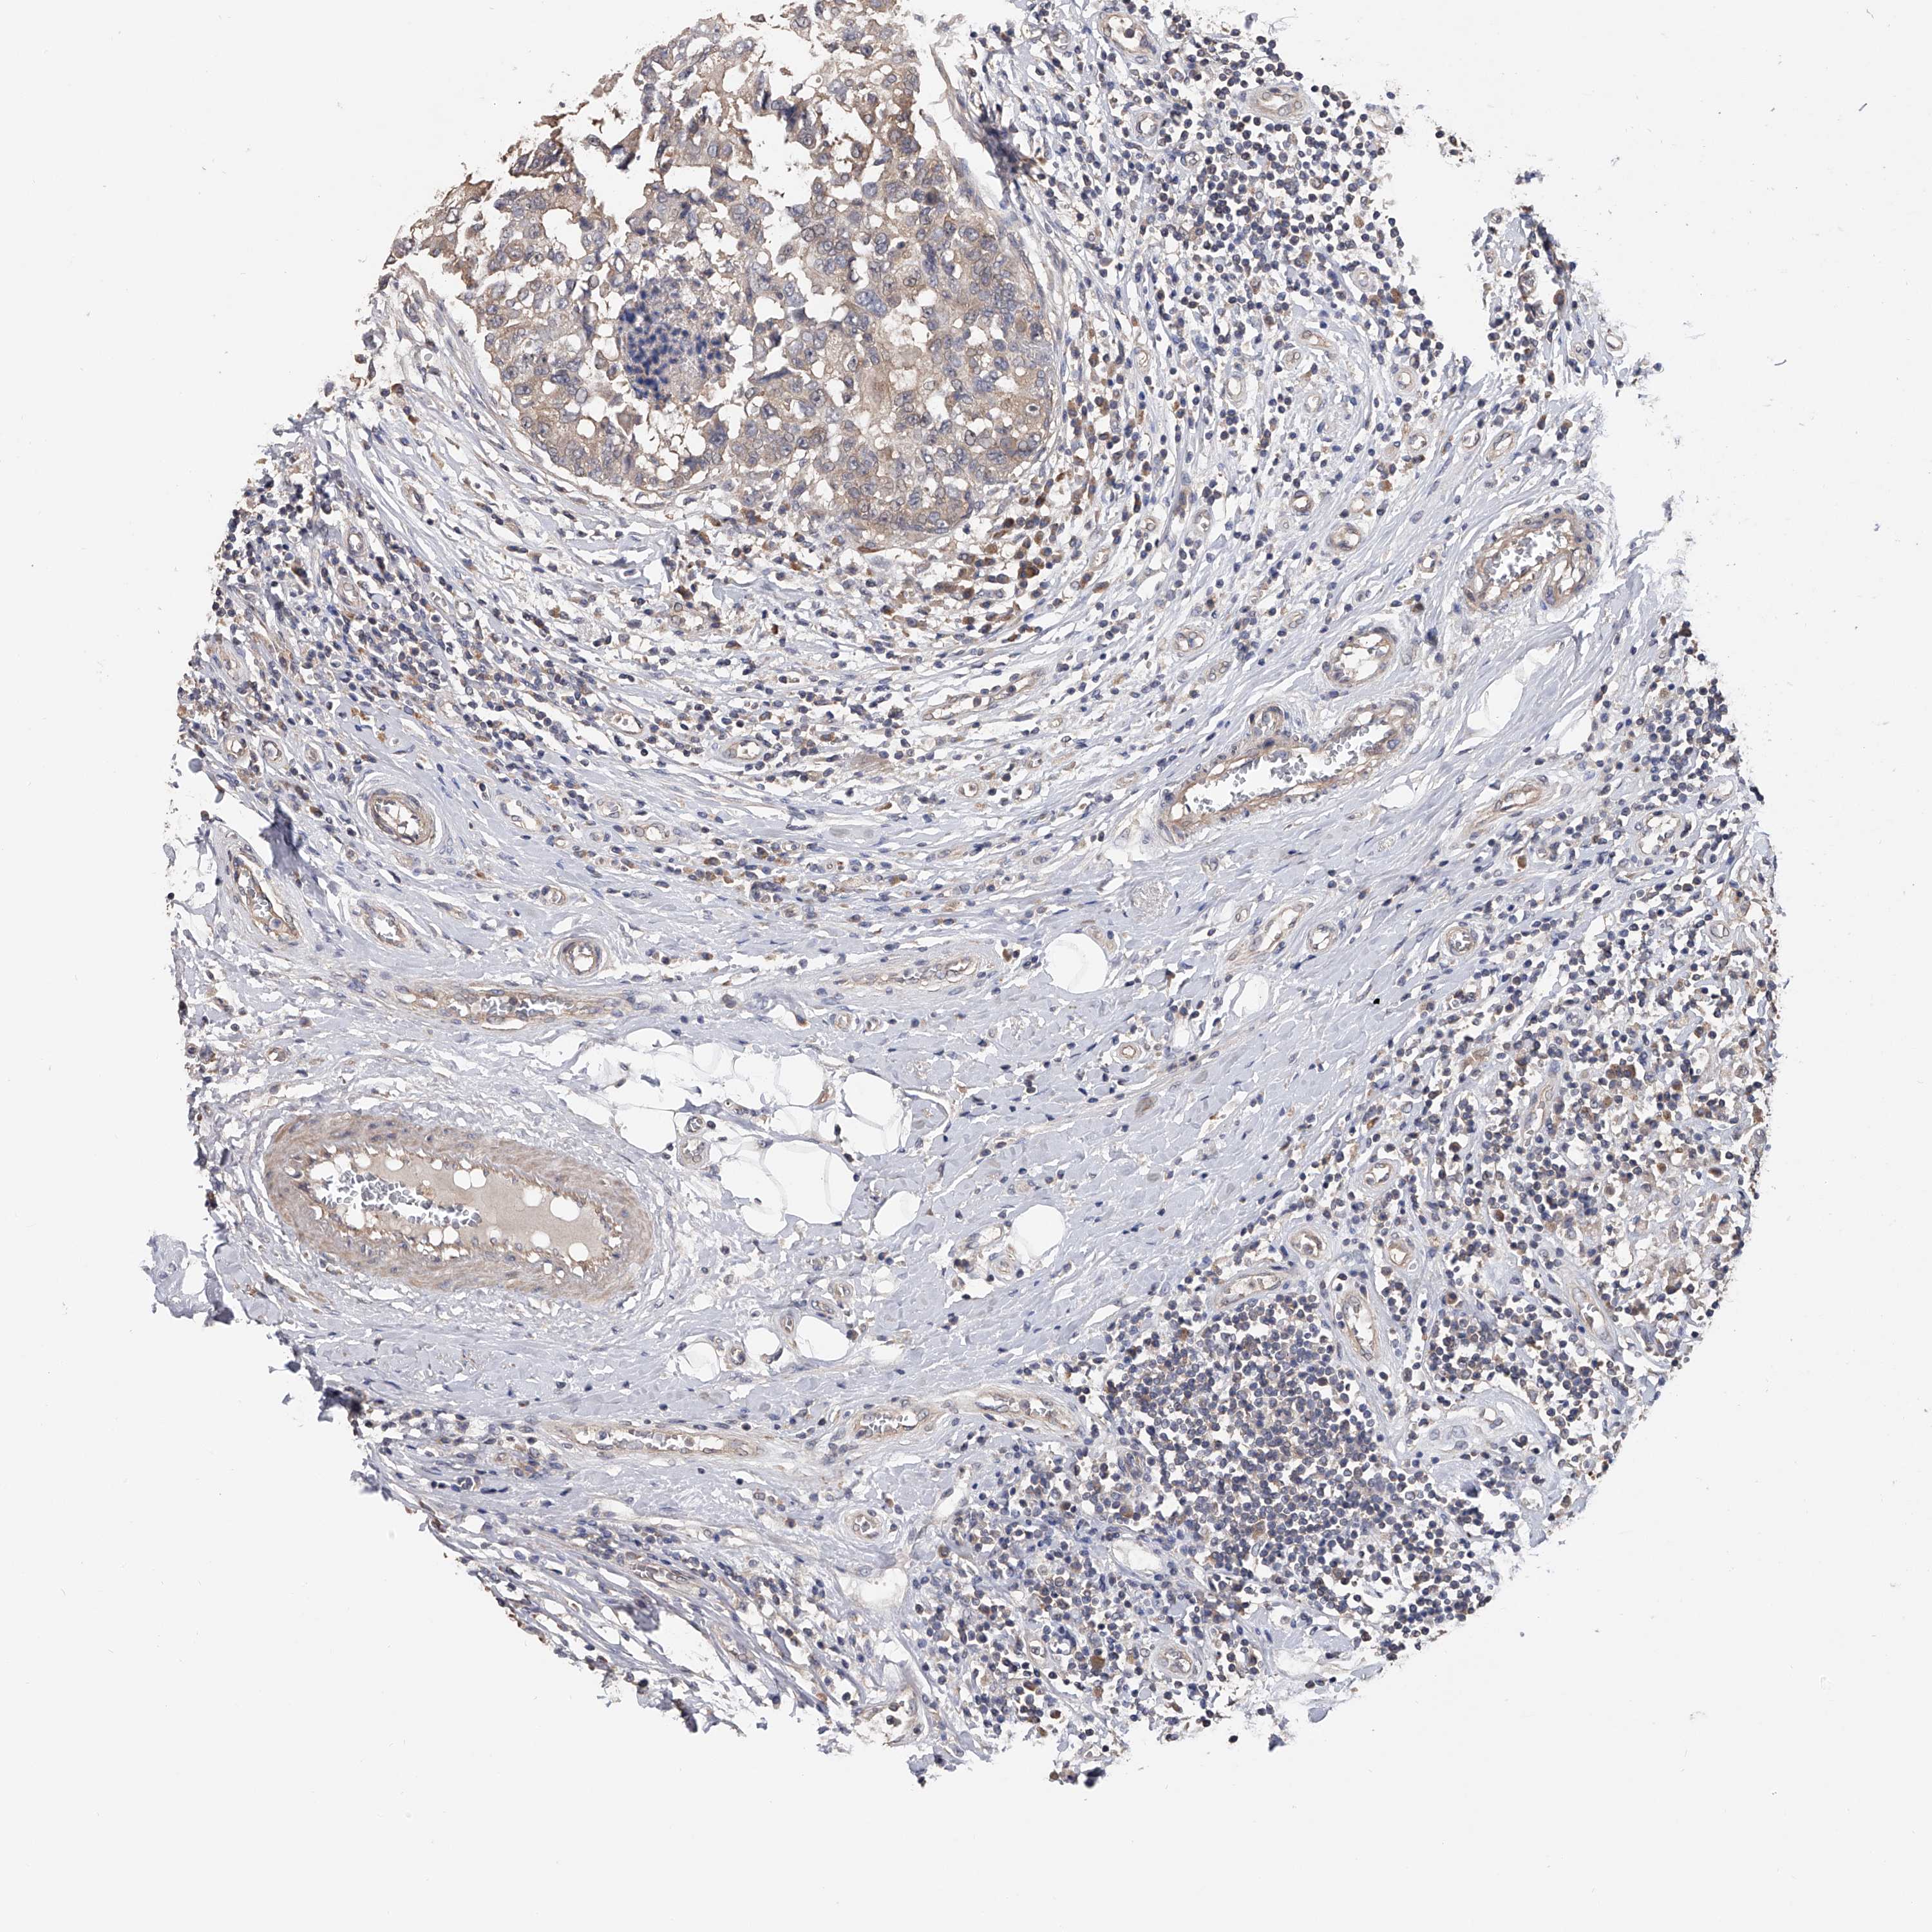

CANCER BREAST CANCER Show tissue menu

BRCA TCGA BRCA VALIDATION PROTEIN EXPRESSION